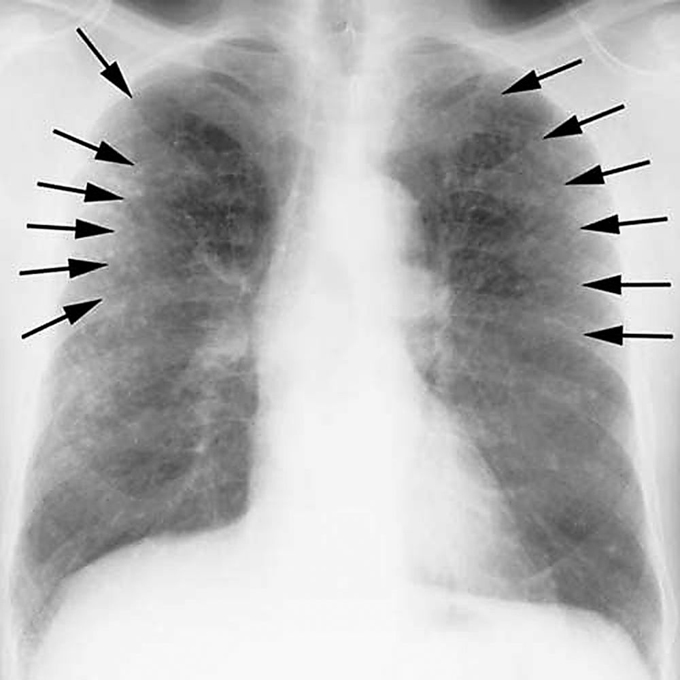

Pleural Changes Chest XRay MedSchool Chest X Ray Asbestos Exposure Advanced asbestosis appears as excessive whiteness in your lung tissue. Web asbestosis onset occurs ≥10 years following the initial exposure to asbestos. Web asbestos exposure is related to restrictive and obstructive lung function impairment. Web asbestosis is a form of interstitial pulmonary fibrosis caused by asbestos exposure. If the asbestosis is severe, the tissue in both. They represent areas of. Chest X Ray Asbestos Exposure.

Pleural Plaques Causes, Symptoms, Diagnosis, Treatment Chest X Ray Asbestos Exposure Advanced asbestosis appears as excessive whiteness in your lung tissue. If the asbestosis is severe, the tissue in both. Even in the absence of. They represent areas of hyaline thickening. Web asbestos exposure is related to restrictive and obstructive lung function impairment. Web asbestosis is a form of interstitial pulmonary fibrosis caused by asbestos exposure. Web asbestosis onset occurs ≥10. Chest X Ray Asbestos Exposure.